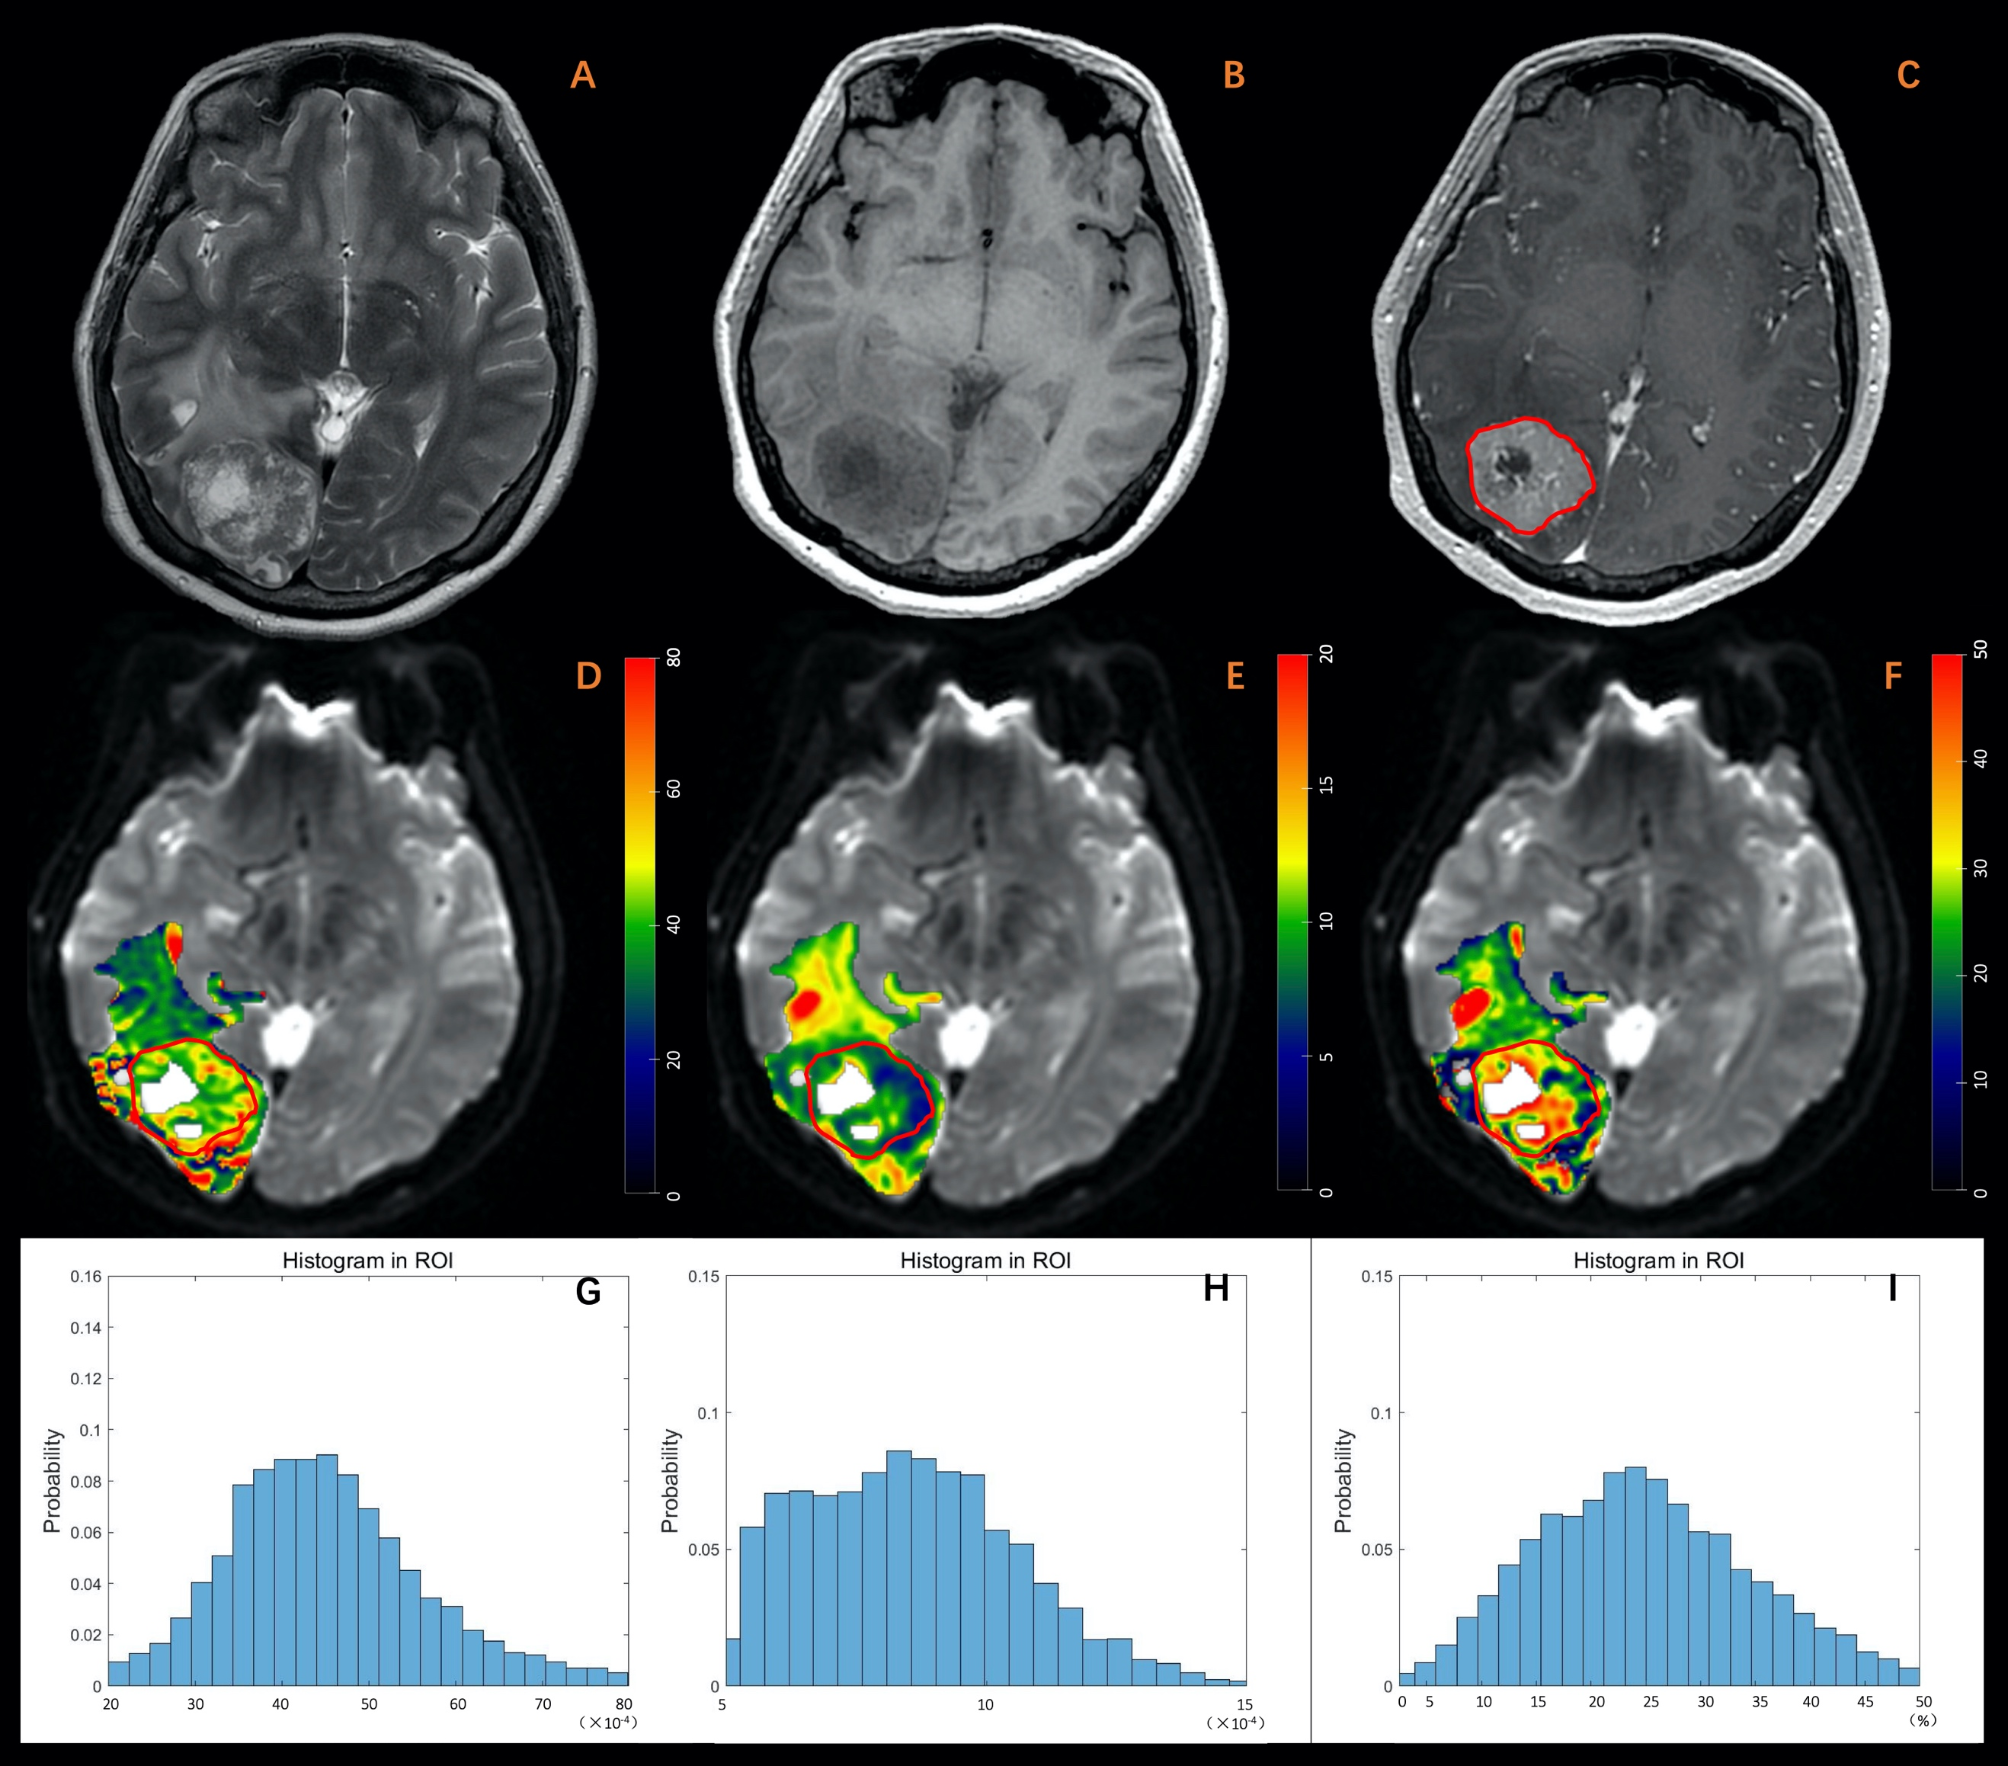

Fig. 3

A 34-year-old female diagnosed with brain metastasis originating from breast cancer. (A) T2W imaging. (B) T1W imaging. (C) Contrast-enhanced T1W imaging. (D) Dfast (×10-4mm2/s). (E) Dslow (×10-4mm2/s). (F) frac (%). (G-I) Histogram plot of Dfast, Dslow, and frac of the enhanced tumor area. The MRI examination revealed an irregular lesion with a well-defined margin in the sub-cortex of the right occipital lobe. The lesion exhibited diffuse enhancement, marked in red, and appeared hyper-intense on T2-weighted imaging, hypo-intense on T1-weighted imaging, and was accompanied by peritumoral edema. Additionally, central necrosis was observed within the lesion. Parametric values obtained from histogram analysis of the enhanced tumor area are as follows: Dfast: mean: 45.38, entropy: 3.80, skewness: 0.70, kurtosis: 4.42; Dslow: mean: 8.55, entropy: 4.09, skewness: 0.47, kurtosis: 2.85; frac: mean: 25.15, entropy: 3.76, skewness: 0.49, kurtosis: 3.31.